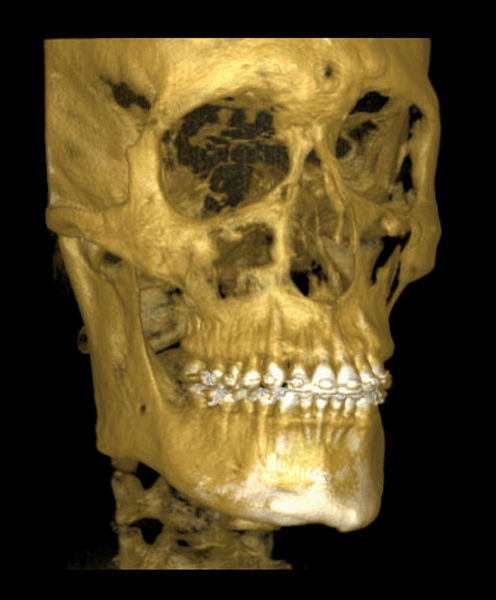

Documentações Ortodônticas

É um conjunto de exames (radiografias, fotografias , análises, modelos) que são imprescindíveis para que juntamente com a anamnese, exame clinico, exame funcional seja feito o diagnóstico e planejamento ortodôntico .Além disso, servem como um registro para comparação e avaliação dos resultados do tratamento ortodôntico e como documentação legal.